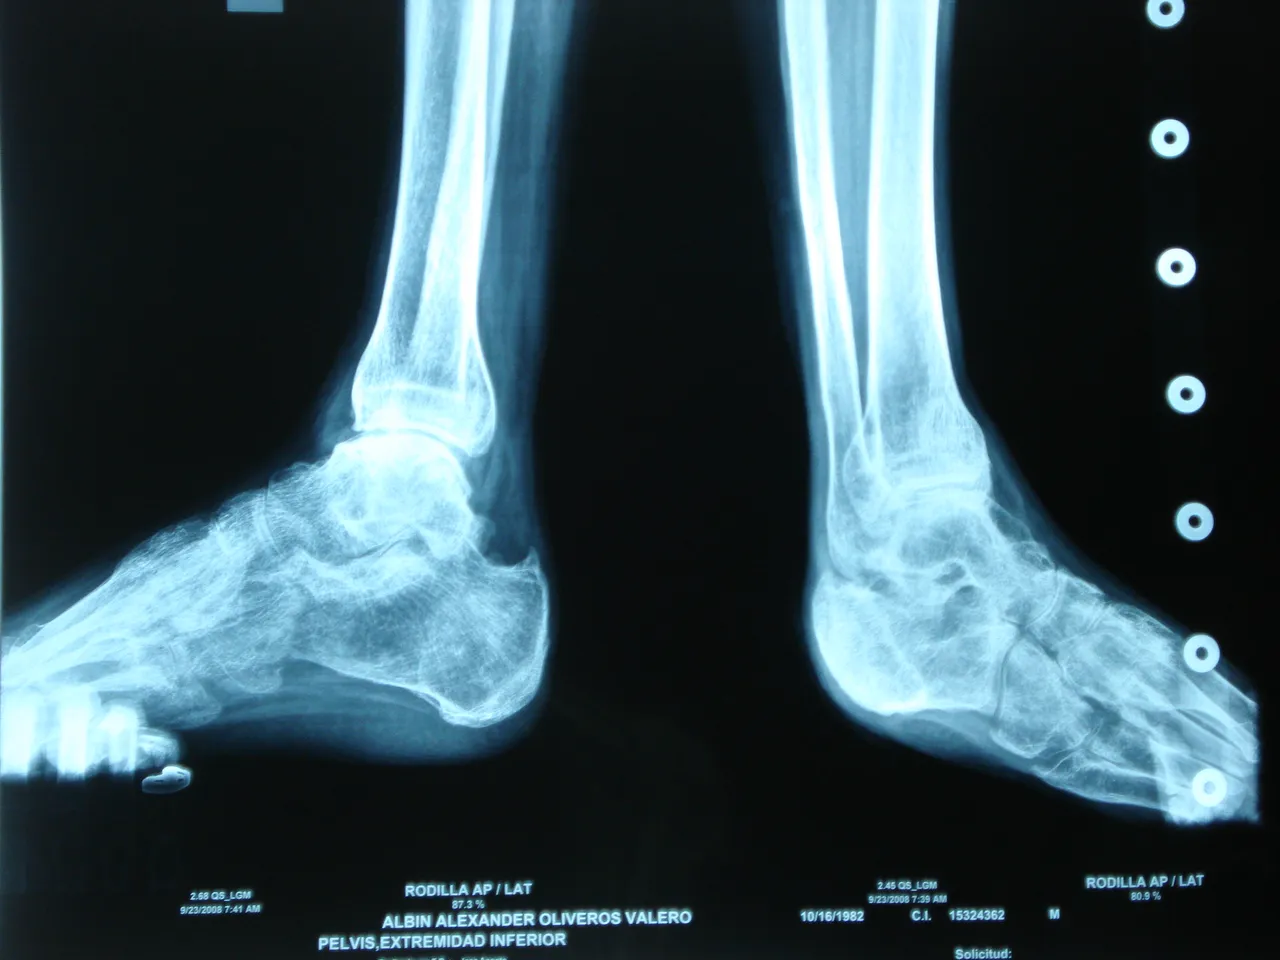

A diabetic foot is a clinical disorder of neuropathic origin (involvement in the nerves) and induced by hyperglycemia (high sugar), in which with or without coexistence of ischemia (lack of blood supply), and previous traumatic trigger, produces injury and / or ulceration of the foot.

The foot of the diabetic should be considered a risk foot, since it is more susceptible to suffer certain types of injuries whether intrinsic or extrinsic. In a significant number of chronic diabetics appear on their feet lesions characterized by trophic disorders of the skin and osteoarticular architecture of the foot It is estimated that half of the amputations of lower limbs in the world occurs in diabetics, diabetes being the The first cause of non-traumatic amputations in developed countries. 15% of patients with diabetes will develop an ulcer throughout their lives.